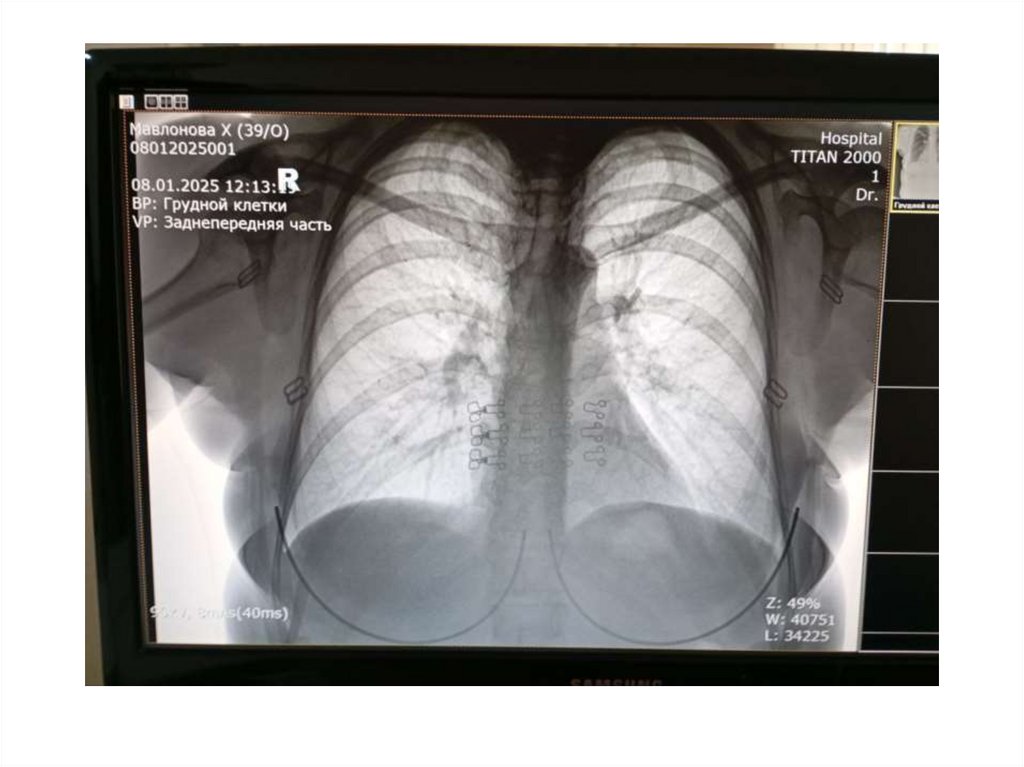

Bemor Mavlanova Xurshidabonu • 24/09/1986 yil

• Bemor Mavlanova Xurshidabonu

• 24/09/1986 yil

• 2024-yil 20-apreldan Latent tuberkulyoz bilan

davolangan

• 2024-yil 24-oktyabrdan ikkala o’pkalar o’choqli

tuberkulyozi infiltratsiya davri BK abc bilan 1qator dorilarini ichishni boshladi

• 2025-yil 11-yanvardan 1-qator to’ldiruv

bosqichni boshladi

• Ammo bemorda 37,0 C temperatura

kuzatilyapti

• Hamrox kasalligi yo’g’on ichak yarasi bor